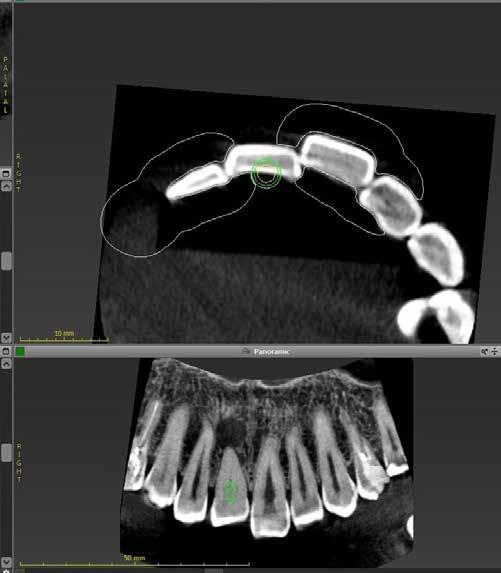

1. a–f ábrák: A cingulumon keresztül gömbfúróval kialakított hozzáférés a trepanációs kavitás labiális irányba történő túlzott mértékű kiterjesztését eredményezheti, és ez lényegesen növelheti a perforáció esélyét (a). A guttapercha átsejlik a lágyrészek alatt (b). Klinikailag igazolt perforáció (c). A preoperatív sagittális irányú CBCT-szeleten jól látható a labiális perforáció (d). Labiális irányú perforáció (fekete nyíl; e). A tényleges gyökércsatorna (piros nyíl; f).

A frontfogakban történő hozzáférési nyílás kialakítása

A frontfogakban a hozzáférési nyílás kialakítását hagyományosan a fogak linguális vagy palatinális felszínén, a cingulumon keresztül egy gömbfúró segítségével kezdjük. A linguálisan elhelyezkedő kiemelkedés teljes eltávolítása, továbbá a pulpaszarvak teljes feltárása egy háromszög alakú hozzáférési nyílást eredményez. 7 Ezt a módszert a fogak esztétikai megjelenésének megőrzése érdekében fejlesztették ki. Ez azonban időnként a saját foganyag indokolatlan eltávolításával, a trepanációs kavitás labiális irányba történő túlzott kiterjesztésével, perforációval, valamint a fog kritikus helyen, a pericervikális dentin (PCD) területén történő meggyengítésével jár (1. a–f és 2. a-b ábrák). 19 Felmerült, hogy a pericervikális dentin rendkívül fontos szerepet játszik a rágóerő gyökerek irányába történő továbbításában, és elképzelhető, hogy a gyökérkezelt fogak hosszú távú megtartása szempontjából a legfontosabb tényező az ép pericervikális dentin megőrzése lehet. 20 A cingulumon keresztül történő hozzáférési nyílás

5. a–l. ábrák: Az incisális élen keresztül kialakított hozzáférés lehetővé teszi a pericervikális dentin megőrzését. Kalcifikáció esetén CBCT-felvétel készítése hasznosnak bizonyulhat a hozzáférési nyílás tervezése során (a–d) . Minden fog koronai helyreállítása a gyökértömés elkészítésével egyidejűleg történt. A négyéves (e–h) és a kétéves (i–l) kontrollok alkalmával készített röntgenfelvételeken teljes gyógyulás látható. Mindkét fog tünetmentes és funkcióképes volt. (Dr. Viraj Vora esetei)

Szuvas lézión keresztül történő hozzáférés (a). A fog koronai helyreállítása a gyökértömés elkészítésével egyidejűleg történt (b és c). (Dr. Dale Jung esete)

kialakítása során fennáll a fog labiális irányú perforációjának veszélye, mivel ilyenkor a foganyag elvételét labiális irányú fúrótartással kezdjük. Nemrégiben újragondolták a

sálisabb megközelítéssel javasolták. 21,22 Az új ajánlásban azt javasolják, hogy a frontfogakban történő hozzáférési nyílás kialakítását a cingulumtól távolabb, inkább az incizális él közelében kezdjük meg 19. Ez lehetővé teszi a lehető legtöbb pericervikális dentin megőrzését és kizárólag a legszükségesebb mennyiségű dentin kerül eltávolításra. Emellett ez a kialakítás a cingulumon keresztül történő hozzáféréshez képest egyenesebb hozzáférést biztosít a labiális és a linguális, vagy palatinális csatornákhoz, valamint lehetővé teszi a csatornák hatékonyabb tisztítását. 21 A fogak kopása esetén a hozzáférést az incisális „felszín” közepén alakítjuk ki (3. a-b ábrák) . A frontfogak kezelése során a megfelelő fúró kiválasztása is kiemelkedően fontos szereppel bír. A korábban ajánlott gömbfúrók használata ma már kifejezetten kontraindikáltnak számít. A gömbfúrók használatakor jellemzően egy fordított tölcsér alakú üreg kerül kialakításra. Ezekben az esetekben az üreg egyre szélesebb lesz, ahogy egyre mélyebbre hatolunk a fúrónkkal (2. a-b ábrák) 23 A gömbfúrók helyett olyan fúrók használata javasolt, amellyel elkerülhető lehet a trepanációs kavitás túlzott mértékű kiterjesztése, és amely segítségével a hozzáférési nyílás legszűkebb részét a pericer -

zésére. Ez azért fontos, mert a frontfogak funkcionális megterhelése során – a PCD-nek megfelelően elhelyezkedő területben – jelentős stressz ébred (5. a–l ábrák) 24 Szükség esetén egy CBCT-felvételt is készíthetünk. A 3D-s adatok jelentős mértékben segíthetik a klinikus munkáját a gyökércsatorna koronális vetületének vizualizálásában, és ennek alapján az egyenes vonalú hozzáférés biztosításához szükséges belépési pont meghatározásában (5.

a–l ábrák) . Ha a kofferdám izolálás a szomszédos fogakra is kiterjesztésre kerül, úgy a kezelést végző orvos sokkal magabiztosabban tudja a gyökerek angulációját vizualizálni (3. a-b ábrák)